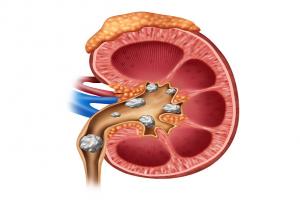

Body part(s) involved-

Esophagus

Stomach

Intestine